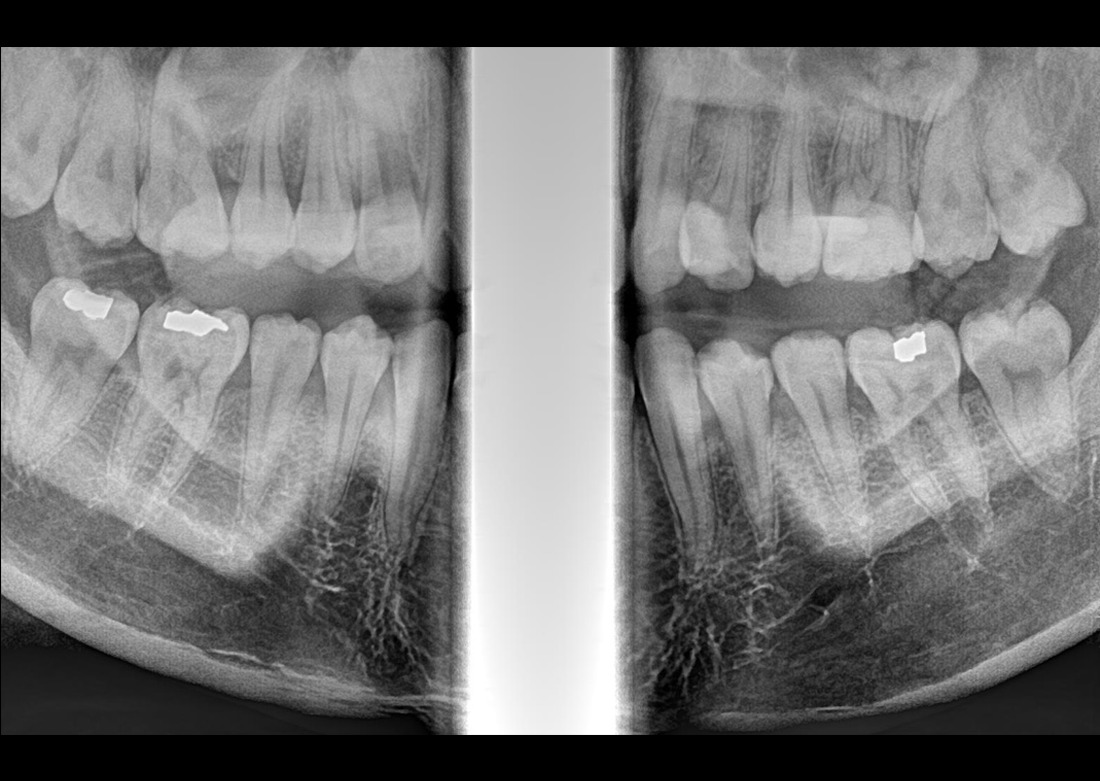

Multi Focus

Egyetlen szkennelés során öt panorámaképet készít, amelyek közül kiválasztható a legjobb minőségű felvétel.

KLİNIKAI KÉPEK

Kiváló diagnosztikai képalkotás több éves tapasztalattal és szakértelemmel.